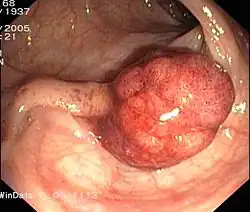

Gestielter Dickdarmpolyp

Gestielter Dickdarmpolyp -

Polypen

Polypen sind makroskopisch sichtbare, meist gestielte Ausstülpungen der Mukosa. Im Laufe mehrerer Jahre können sie entarten und zu Dickdarmkrebs (siehe auch Adenom-Karzinom-Sequenz) führen, und sie werden deshalb (auch im Rahmen von Vorsorgekoloskopien) in derselben Sitzung entfernt.

Tumoren

Bei Tumoren und hier insbesondere dem Dickdarmkrebs (Kolonkarzinom) werden zur genauen feingeweblichen Untersuchung Gewebsproben Biopsien entnommen. Bei nicht mehr operablen Patienten kann endoskopisch bei hochgradiger Einengung ein Stent eingelegt werden, um die Kotpassage zu ermöglichen und einen künstlichen Darmausgang (Anus praeter) zu vermeiden. In einer groß angelegten Studie im Saarland konnte gezeigt werden, dass Personen, die sich innerhalb der letzten zehn Jahre einer vorbeugenden Koloskopie (Krebsvorsorge) unterzogen hatten, deutlich weniger häufig fortgeschrittene Krebsvorstufen hatten als die Personen einer Vergleichsgruppe, die sich zum ersten Mal einer Koloskopie unterzogen (6,1 % zu 11,4 %).[9]